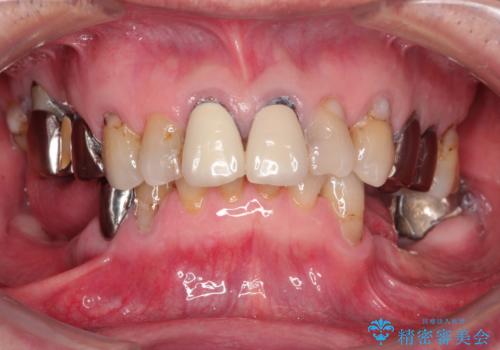

[インプラントオーバーデンチャー] インプラントで奥歯を支える部分床義歯

![[インプラントオーバーデンチャー] インプラントで奥歯を支える部分床義歯の症例 治療前](https://seimitsushinbi.jp/wp/wp-content/uploads/2020/05/79f644293d350fd31fb63c7afa8d4763-500x350.jpg?v=1590579941)